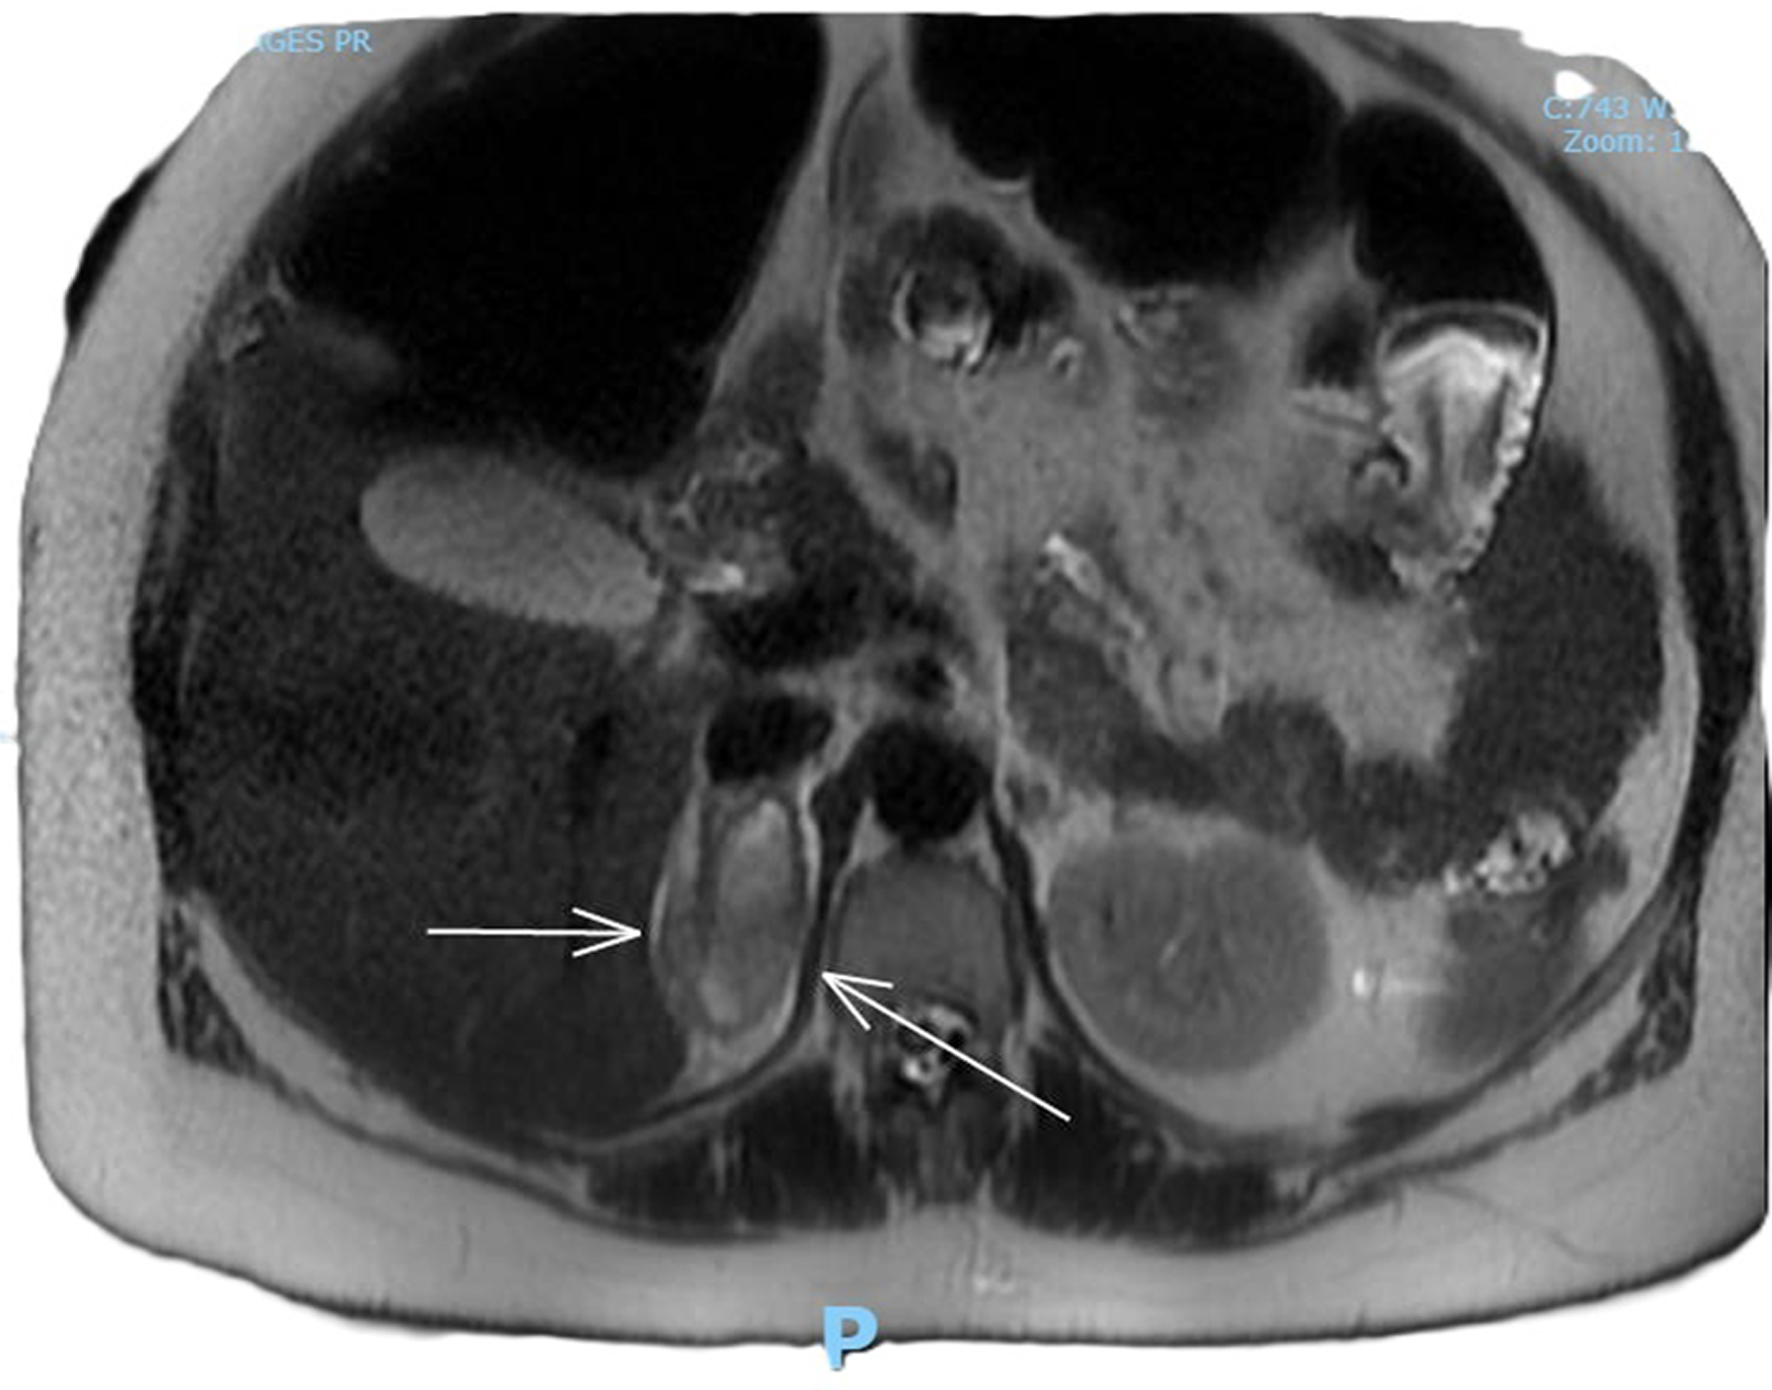

Complete full blood count, coagulation profile, liver function test, renal function test, and amylase were all within normal limits, with a total hemoglobin concentration of 122 g/dL, total leucocyte count of 9,600 mL, normal platelet count, C-reactive protein concentration of 6 mg/L, bile acid concentration of 1.8 µmol/L, creatinine concentration of 46 µmol/L, urea concentration of 1.9 mmol/L, and potassium level indeterminate because of hemolyzed specimen. Urine analysis was negative. Renal ultrasound revealed no evidence of hydronephrosis, mass, or calculi. An obstetric ultrasound performed 1 week prior revealed a live fetus with a normal anterior placenta and appropriate fetal growth with a normal liquor volume and umbilical artery Doppler. Abdominal ultrasound revealed a normal appearance of the gallbladder, no evidence of gallstones, a normal caliber of the common bile duct, and no focal abnormality or ascitic fluid identified with an obscured appendix. The patient was admitted and continued to experience persistent right flank pain with three episodes of vomiting and nausea. She experienced generalized fatigue and malaise 3 days post admission. Intravenous fluids and oral opioids were used to control pain. General surgery colleagues were consulted to rule out surgical causes of acute abdomen and concerns for possible related complications. On review of her investigations, there was a significant decrease in the hemoglobin level to 88 g/dL, a new increase in potassium to 9.6 mmol/L, chloride 117 mmol/L, and a significant steep increase in C-reactive protein levels of 101 and 233 mg/L. An MRI scan of the abdomen (Fig. 1) revealed coronal plane, T2-weighted sequence demonstrating an area of heterogeneous high T2 signal density. An arrow points to enlarged adrenal gland consistent with adrenal hemorrhage. MRI transverse plan (Fig. 2) revealed T2-weighted sequence demonstrating a 44 × 54 × 25 mm lesion centered in right adrenal gland with heterogeneous T2 signal compatible with spontaneous/acute adrenal hemorrhage. A trace amount of fluid surrounding the adrenal gland and right kidney is consistent with SAH. Transverse plane (Fig. 3) high T2 density signals showed enlarged adrenal gland.

Figure 2. MRI transverse plan, T2-weighted sequence demonstrating a 44 × 54 × 25 mm lesion centered in right adrenal gland with heterogeneous T2 signal compatible with spontaneous/acute adrenal hemorrhage. A trace amount of fluid surrounding the adrenal gland and right kidney is consistent with SAH.